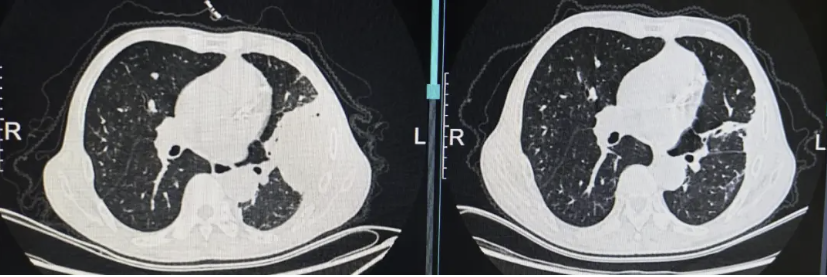

现病史:患者1个月前参加酒席后出现咳嗽、咳脓痰,伴畏寒发热,体温38度,于当地市人民医院就诊,2026年1月19日行胸部CT检查示:两肺感染可能,双肺多发小、微结节,心包、左侧胸腔少量积液(图片1)。予左氧氟沙星输液治疗,仍有发热伴咳嗽咳痰,间断有少量痰血,再次就诊于当地市人民医院,2026年1月31日行气管镜检查,灌洗液mNGS提示:惠普尔养障体 序列数283,小孢根霉 序列数66,建议患者至省会医院进一步就诊。2026年2月5日患者于当地省会医院住院,予静脉输注艾沙康唑抗真菌治疗,2026年2月9日行胸部增强CT检查示:左上胸膜下大片状高密度影伴明显坏死、积气,结合临床符合毛霉病并胸膜侵犯,双侧胸腔少量积液,左侧部分包裹性改变(图片2)。因患者病灶较前增大,病情进展,家属要求转院至上海治疗。

图片2:2026年2月9日当地省会医院胸部增强CT示左上胸膜下大片状高密度影伴明显坏死、积气,结合临床符合毛霉病并胸膜侵犯,双侧胸腔少量积液,左侧部分包裹性改变。